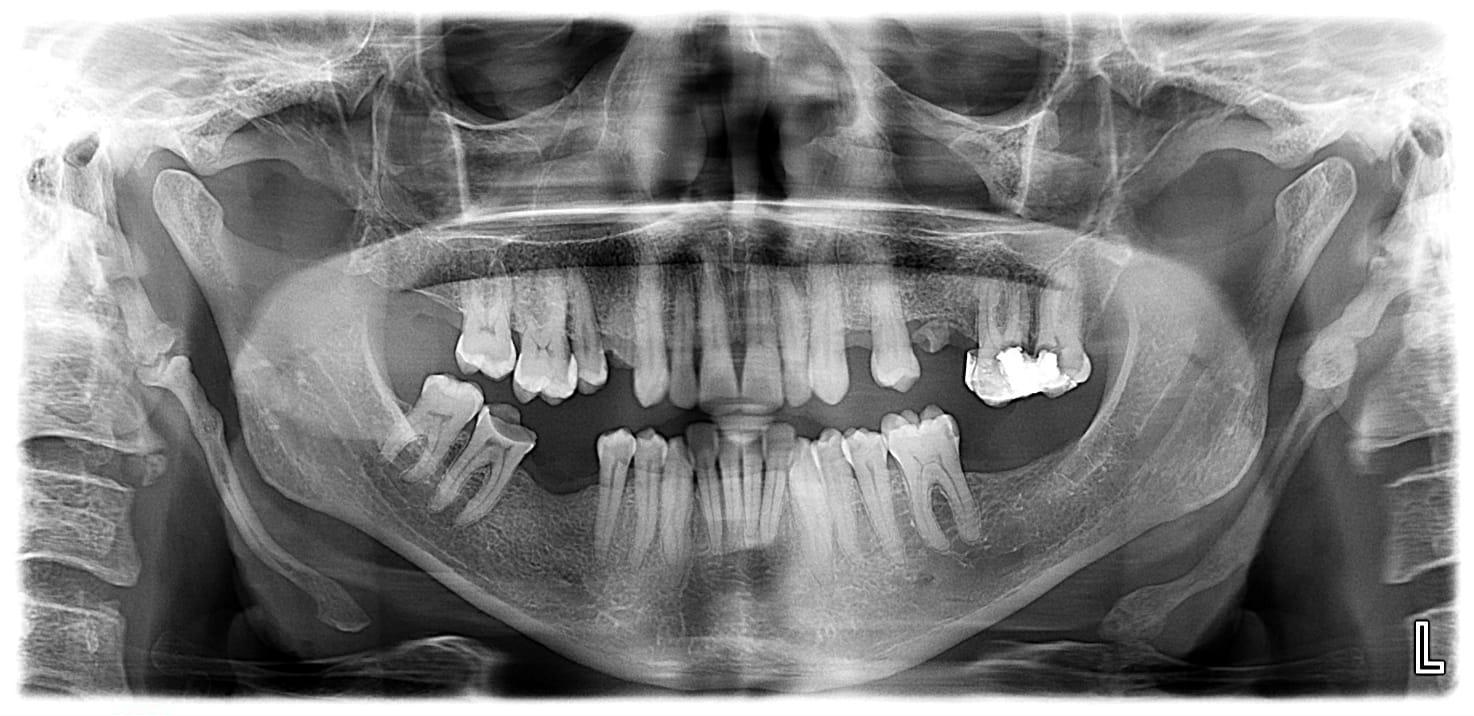

It encompasses various imaging techniques, including traditional x rays such as OPG, CEPH and advanced imaging like Cone beam computed tomography (CBCT).

These methods visualise teeth and bone providing crucial diagnostic information.

Orthopantomogram (OPG)